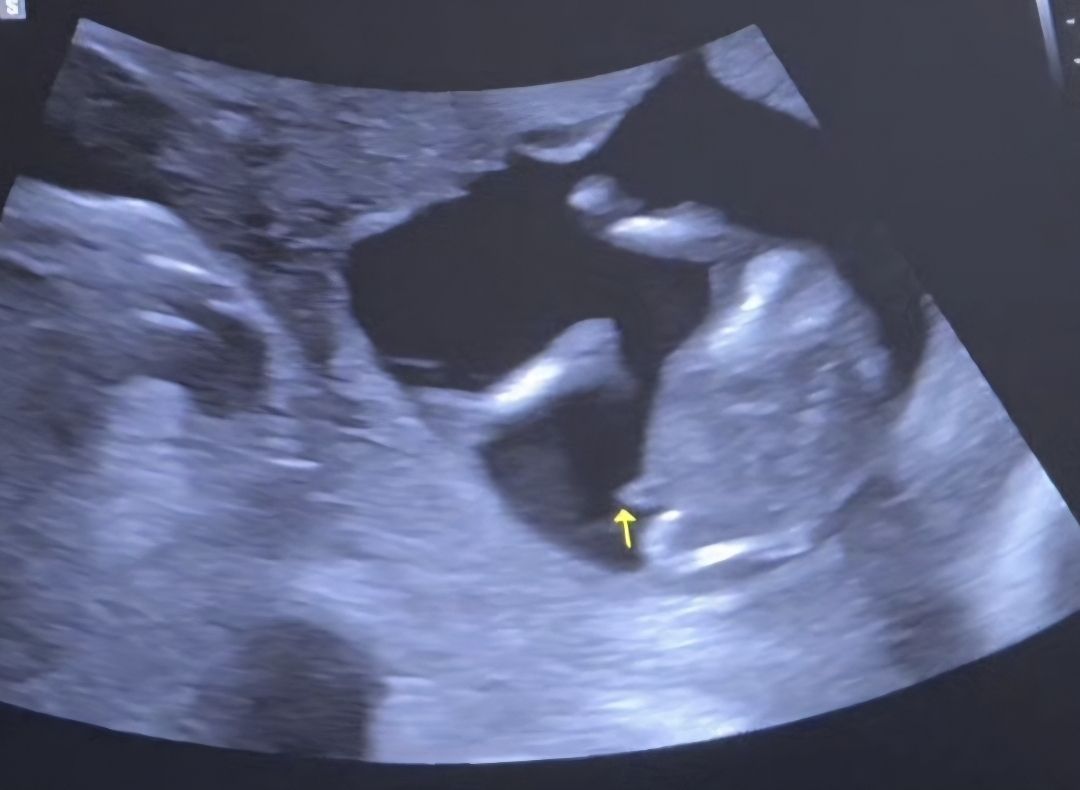

존재감 뿜뿜한 아들..🤣14주 아들맘 당첨💙

니프티검사를 일찍해서 12주에 성별을 알았는데... 초음파로는 14주에 딱 봤는데.. 원장님 왈 : 니프티 안했어도 확실하게 성별 알았겠는데요?? 🤣 존재감 확실한 우리아들.. 잘 자라렴😍 12월 베동맘들 친하게지내용😆